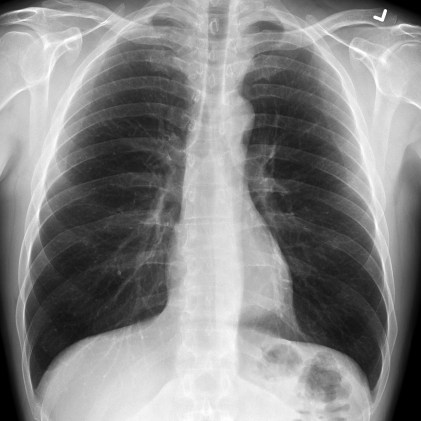

A 60-year-old male presents with a four-day history of abdominal pain secondary to cholangitis. The patient presents in septic shock requiring intravenous fluid resuscitation, empiric broad-spectrum antibiotics and vasopressor support and suffers a PEA arrest prior to disposition to advanced imaging or definitive management.